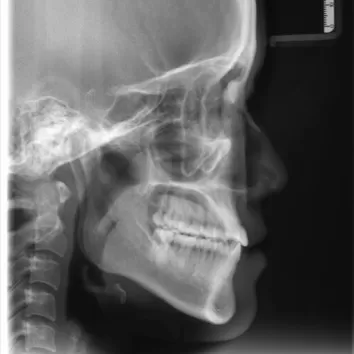

X-rays before treatment

[Panoramic Radiography/Lateral Cephalogram]